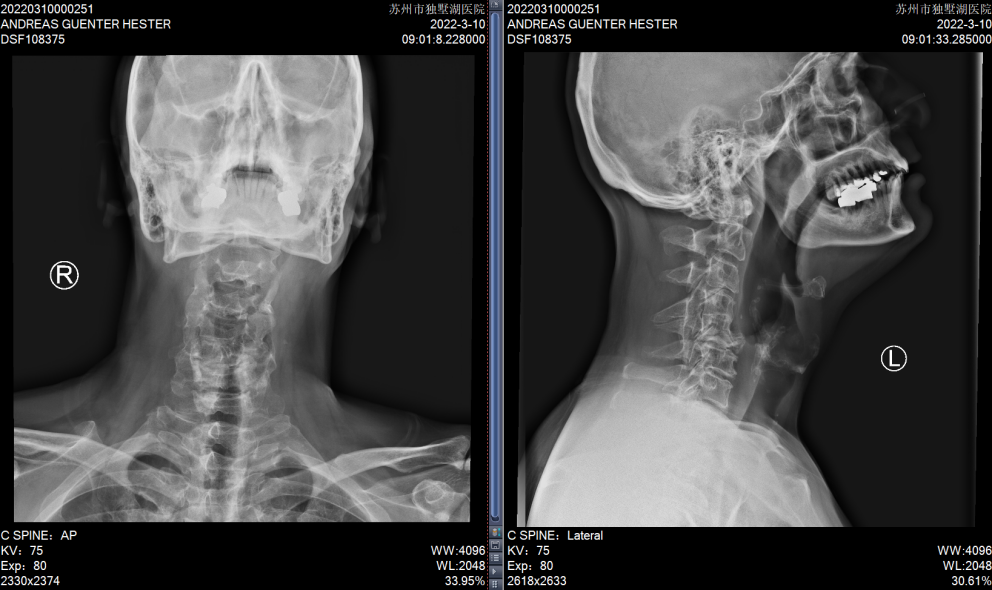

患者C4和C5椎体发育异常

C5/6、C6/7椎间盘突出明显,椎管狭窄,脊髓受压严重

术后复查X片,C5/6和C6/7椎间隙高度恢复满意